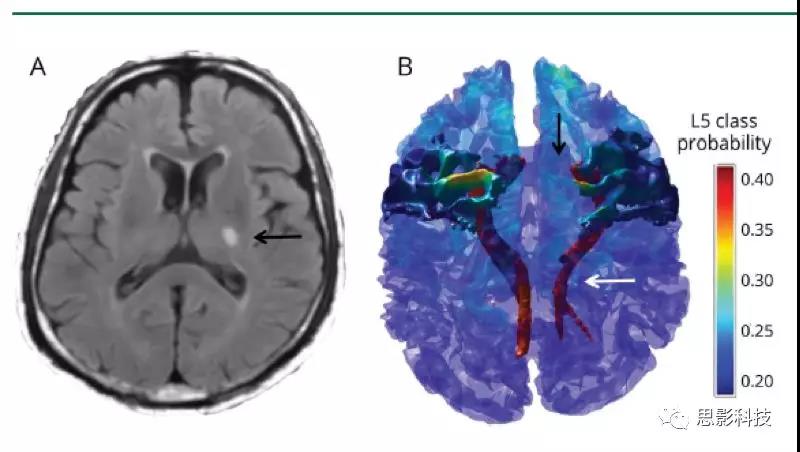

(A)左內(nèi)囊后肢有慢性皮質(zhì)下小梗死的代表性患者的Flair圖像(黑色箭頭)。通過使用彌散張量纖維追蹤術,選擇左內(nèi)囊后肢梗塞點為種子和手動放置的對照種子來重建皮質(zhì)脊髓束(CST)并識別相連的M1,如(B)三維體積渲染所示。由此產(chǎn)生的L5類皮層層狀模式在三維模型上進行了描述,并將L5的T1層類概率圖投影到皮層表面。白色箭頭指示梗死上方和下方的左CST變性;黑色箭頭指示所連接的左M1的萎縮。